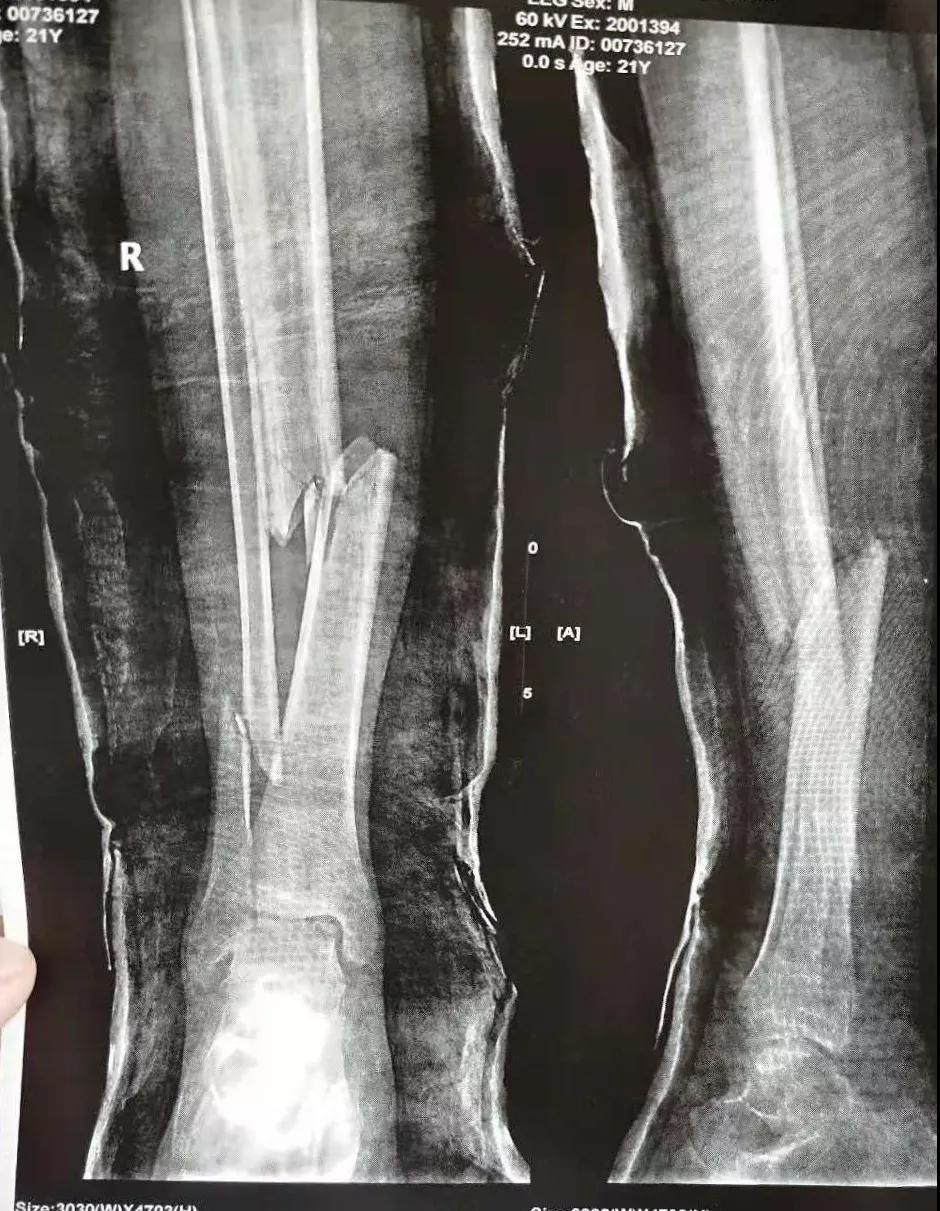

这名21岁的男性患者一个月前因车祸致伤,在当地某三甲医院确诊为右胫腓骨粉碎性骨折,骨折移位明显,建议手术治疗,因既往患严重慢性再生障碍性贫血病史16年,一般状况差,需长期输注血液制品维持三系细胞水平,麻醉及手术风险极高。虽经当地积极内科治疗,患者一般状况仍差,无法耐受手术治疗。患者及家属经多方打听,抱着最后一丝希望来到六合彩生肖 骨二科求治。

骨二科张延平主任接诊后经仔细询问病史,详细阅读近期X线、CT等病历资料,认为患者骨折移位明显,目前骨折无任何愈合迹象,若保守治疗,骨折将无法愈合,后期不能下地活动,严重影响患者生活质量。同时患者合并慢性再障,血常规结果各项指标均极低,围术期发生麻醉意外、大出血、感染等风险极高;而六合彩生肖 作为西安市级最大的三甲综合医院,综合实力深厚,既往相关疾病治疗经验丰富,多次通过多学科诊治为合并复杂内科疾病患者保驾护航,为患者创造手术时机,提高患者生活质量,遂将患者收住院。住院后,立即成立了由张延平主任、杨寅副主任、山卉护士长、梁晨主治医师、刘邦定主治医师、李鑫护师组成的手术治疗小组。经初步检查,患者血常规结果较当地检验结果更差,三系细胞均极低,其中血小板仅为1(正常值为100-300),血红蛋白55g/L。遂立即请血研所李罡灿主任医师会诊,给予升高白细胞、纠正贫血、升高血小板等治疗,经积极治疗患者血常规各项指标均较入院时改善。张延平主任再次组织由血研所李罡灿主任医师、麻醉科崔晓岗主任、感染科付建军主任、药剂科韩小年副主任药师等参加的术前讨论。讨论后一致认为患者目前各项指标虽然较入院时改善,但因其慢性再障病史长,骨髓造血及储备能力极差,围术期发生大出血、伤口感染甚至全身感染等风险仍极高,术中及术后需准备大量血小板防止大出血,同时需高度警惕手术切口、取骨区术后发生感染。为尽快为患者施行手术,治疗小组积极联系输血科为患者备血,并为患者制定了围术期抗感染方案;在六合彩生肖 输血科存血量严重不足的状态时,输血科张养民主任亲自联系市中心血站为患者准备手术中及术后所需的血小板制品。手术小组为患者制定了周密的手术方案及风险预案,10月31日,在麻醉科王永宏副主任医师、手术室高洁、赵耀护师的配合下,为患者施行了右胫骨粉碎性骨折切开复位、髂骨取骨植骨内固定术,手术历时70分钟,安全返回病房。术后患者渗血多,1周内连续每日平均渗血超过100ml,并出现发烧,最高39℃,复查血常规三系细胞较术前再次明显降低。李罡灿主任医师、付建军主任、韩小年副主任药师多次来科会诊,及时调整患者的治疗方案,输血科再次为患者的救治提供了强有力的支援和保障。在山卉护士长带领的护理团队精心护理下,患者未发生压疮等卧床并发症。目前该患者术后恢复良好,已出院进行下一步康复治疗。